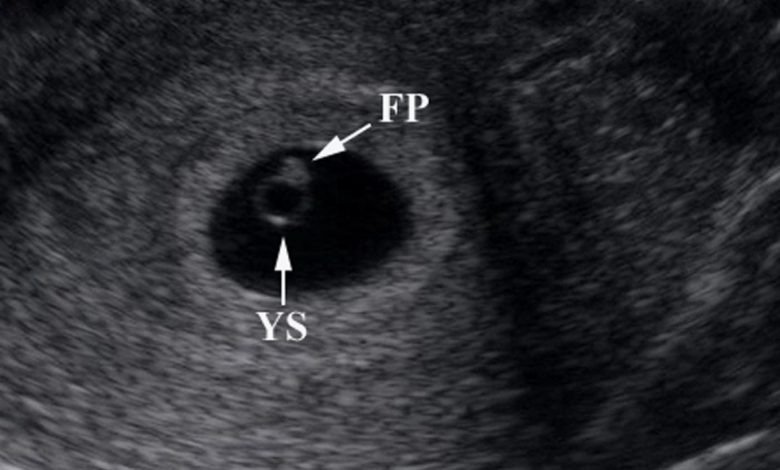

كيف يظهر كيس الحمل في السونار؟

عندما يتعلق الأمر بالحمل والأشهر الأولى من الحمل، فإن معرفة متى يظهر كيس الحمل في السونار أمر مهم للغاية.

عادةً ما يظهر كيس الحمل في السونار بعد حوالي 5-6 أسابيع من انقطاع الدورة الشهرية. ومع ذلك، قد يختلف هذا من امرأة لأخرى حسب عوامل مختلفة مثل طول دورة الحيض وتوقيت التبويض.

عند إجراء فحص سونار، ستستخدم الموجات فوق الصوتية لإنشاء صورة للجنين والكيس الذي يحتضنه. في بداية فترة الحمل، يكون حجم كيس الحمل صغيرًا جدًا وصعبًا رؤيته بوضوح. ولكن مع مرور الوقت، ينمو الكيس ويصبح أكبر وأكثر وضوحًا في السونار.

من المهم أن يتم إجراء السونار بواسطة محترف ذو خبرة للحصول على صورة واضحة ودقيقة. قد يتم إجراء السونار عبر المهبل (transvaginal) في المراحل المبكرة من الحمل، حيث يتم إدخال جهاز سونار صغير في المهبل للحصول على صورة دقيقة للكيس الحمل. بعد ذلك، يتم استخدام السونار عبر البطن (transabdominal) في المراحل اللاحقة من الحمل.